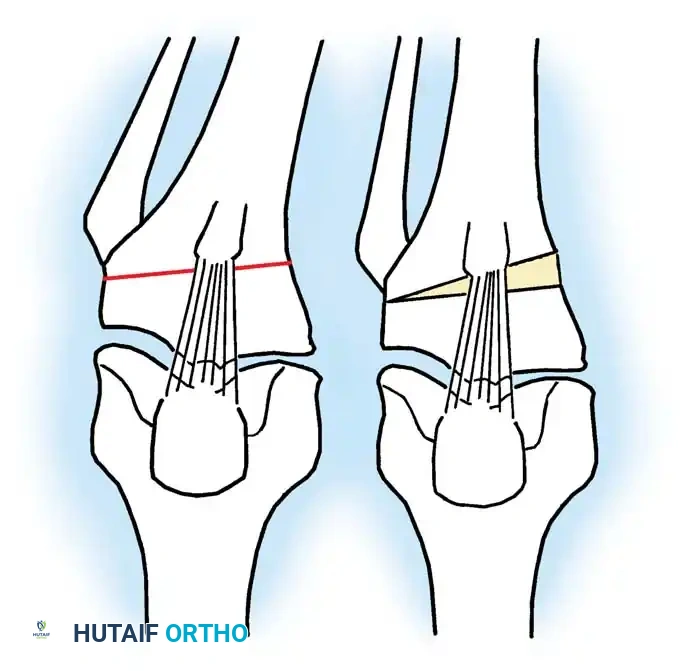

High Tibial Osteotomy (HTO)

HTO is primarily indicated for medial compartment osteoarthritis associated with varus deformity. The goal is to shift the mechanical weight-bearing axis slightly lateral to the midline of the knee joint (the Fujisawa point, typically 62% of the tibial width from the medial edge).

Surgical Approaches:

1. Lateral Closing Wedge HTO: Involves removing a laterally based wedge of bone from the proximal tibia and fixing the osteotomy with a plate or staples. It requires a fibular osteotomy or proximal tibiofibular joint disruption.

2. Medial Opening Wedge HTO: Increasingly popular due to the avoidance of the peroneal nerve and preservation of bone stock. A medial osteotomy is created, opened to the desired correction angle, and stabilized with a rigid locking plate. The void may be filled with allograft or synthetic bone substitute.

Surgical Atlas: Osteotomy and Realignment Biomechanics

The following radiographic and illustrative figures detail the preoperative planning, biomechanical axes, and intraoperative fixation strategies critical for successful osteotomies around the knee.

Preoperative templating is mandatory. The mechanical axis must be drawn from the center of the femoral head to the center of the ankle mortise. The degree of correction is calculated to ensure the new weight-bearing line passes through the targeted compartment.